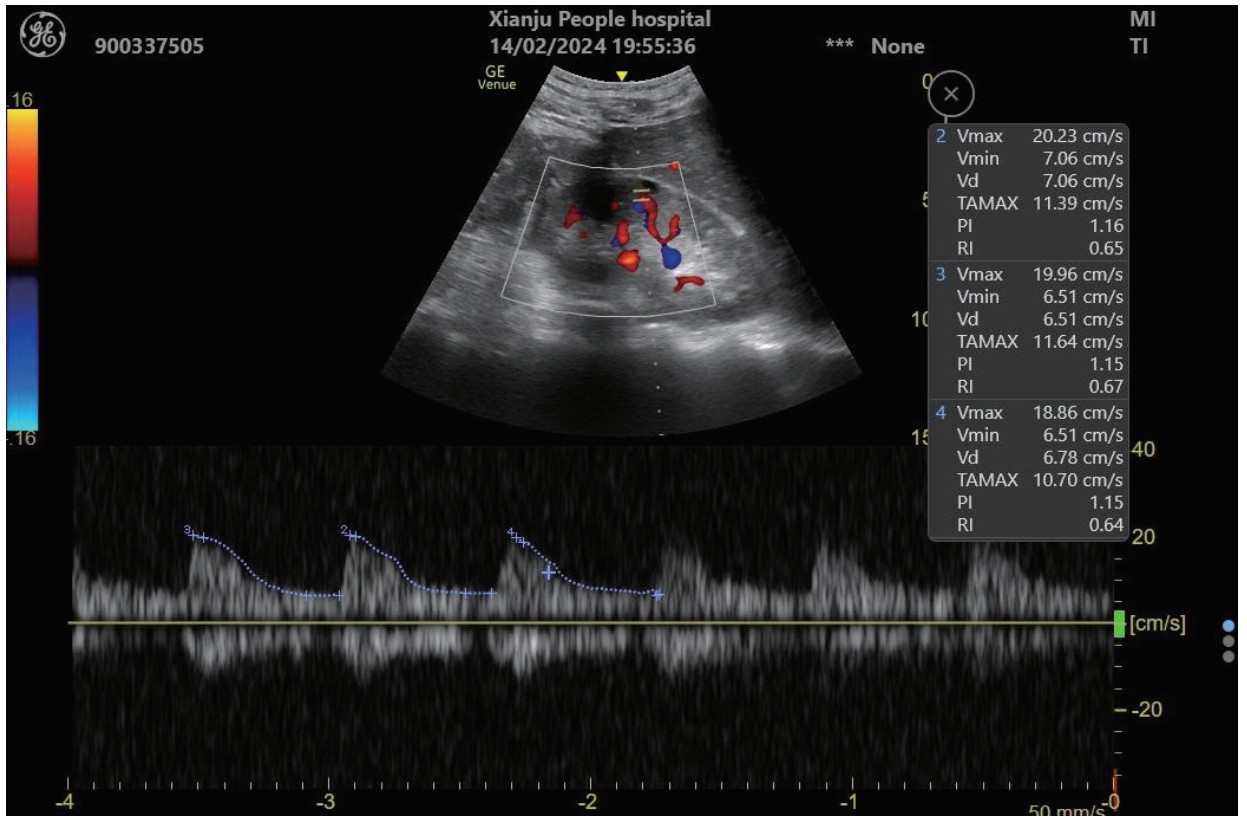

1.2.4 RRI值超声测定在患者入科后0 h(30 min内)、12 h、24 h和48 h进行采血并进行超声检查,超声检查均由具备超声资质的熟练的超声操作者进行。超声设备为急重症移动型超声VenueTM(生产厂家:GE Healthcare,产地:美国),测定时选择肾小叶间动脉进行,探头频率为3.5~6.0 MHz,测定指标包括收缩期峰值流速(peak systolic velocity, PSV)、舒张末期流速(end-diastolic flow velocity, EDV),通过计算公式RRI=(PSV-EDV)/PSV,计算得到RRI值,经由系统可自动计算数值,左右肾各测量3次后取平均值。超声检测见图 1。

|

| 注:PSV为收缩期峰值流速=Vmax;EDV为舒张末期流速=Vmin;RRI为肾动脉阻力指数 图 1 RRI超声测定 |

|

|